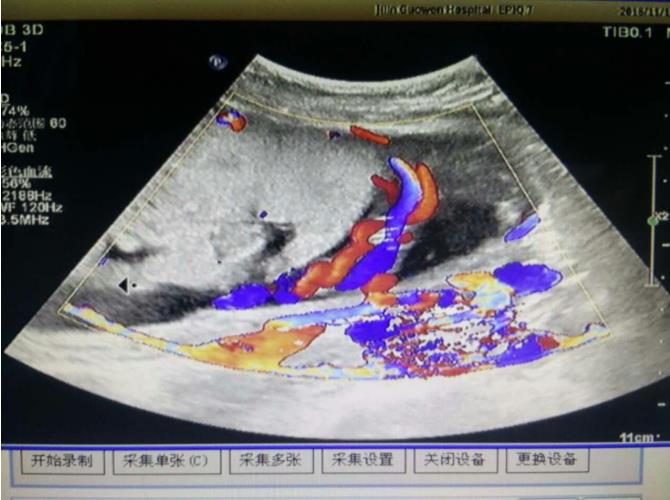

為該患常規(guī)檢查臍帶入口時發(fā)現(xiàn)臍帶入口位于胎盤下緣邊緣,胎兒超聲檢查無陽性發(fā)現(xiàn)。常規(guī)掃查右卵巢時,發(fā)現(xiàn)右卵巢旁可見腎臟回聲(正常情況下,右卵巢旁是不會掃查到腎臟回聲的),大小、形態(tài)如常,CDFI:腎內(nèi)血流灌注尚可,故囑患者左側(cè)臥位,顯示孕婦右腎位置、大小及形態(tài)正常,囑孕婦右側(cè)臥位,發(fā)現(xiàn)脾臟下方無腎臟回聲,故考慮該患左腎游走腎。該患于2016年12月2日復(fù)查,結(jié)果如前。